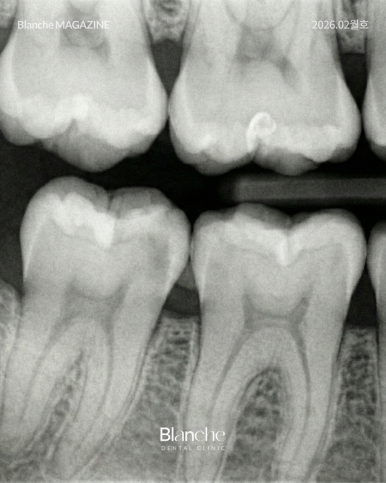

"여기 썩었네요"라는 말 한마디보다 구강 카메라로 찍은

사진과 엑스레이 영상을 대조하며 보여주는 치과가 신뢰할 만합니다.

환자가 자신의 구강 상태를 객관적으로 이해할 수 있을 때

비로소 과잉진료에 대한 불안감도 사라질 수 있습니다.